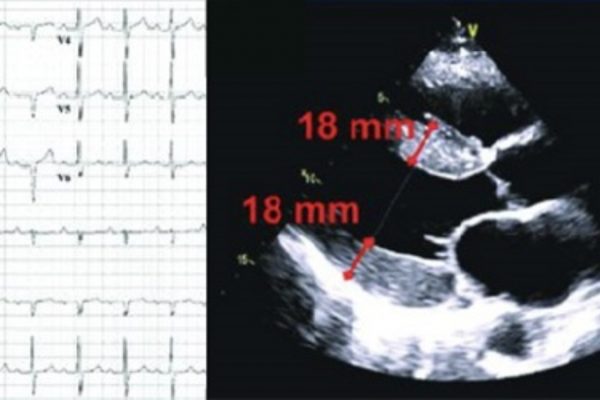

“Quella macchinetta mi ha salvato le penne”: Francesca e il defibrillatore sottocutaneo” di Laura d’Ettole Francesca Musso scopre tardi la sua cardiomiopatia ipertrofica, a 23 anni. Oggi ne ha 30.